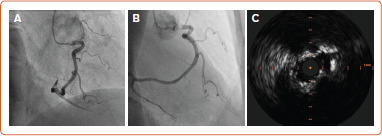

Stent underexpansion (SU) and aorto-ostial lesions (AOL) are challenging conditions commonly faced during clinical practice in the setting of percutaneous coronary interventions. Compared to other interventional settings, both SU and AOL are associated with an increased risk of immediate and late events following percutaneous coronary intervention. Several specific strategies including the systematic use of intracoronary imaging and dedicated techniques for lesions' preparation and calcium debulking have been described. This narrative review summarises the currently available options for the diagnosis and treatment of both SU and AOL, highlighting the potential benefits and limits of each technique in these specific settings.